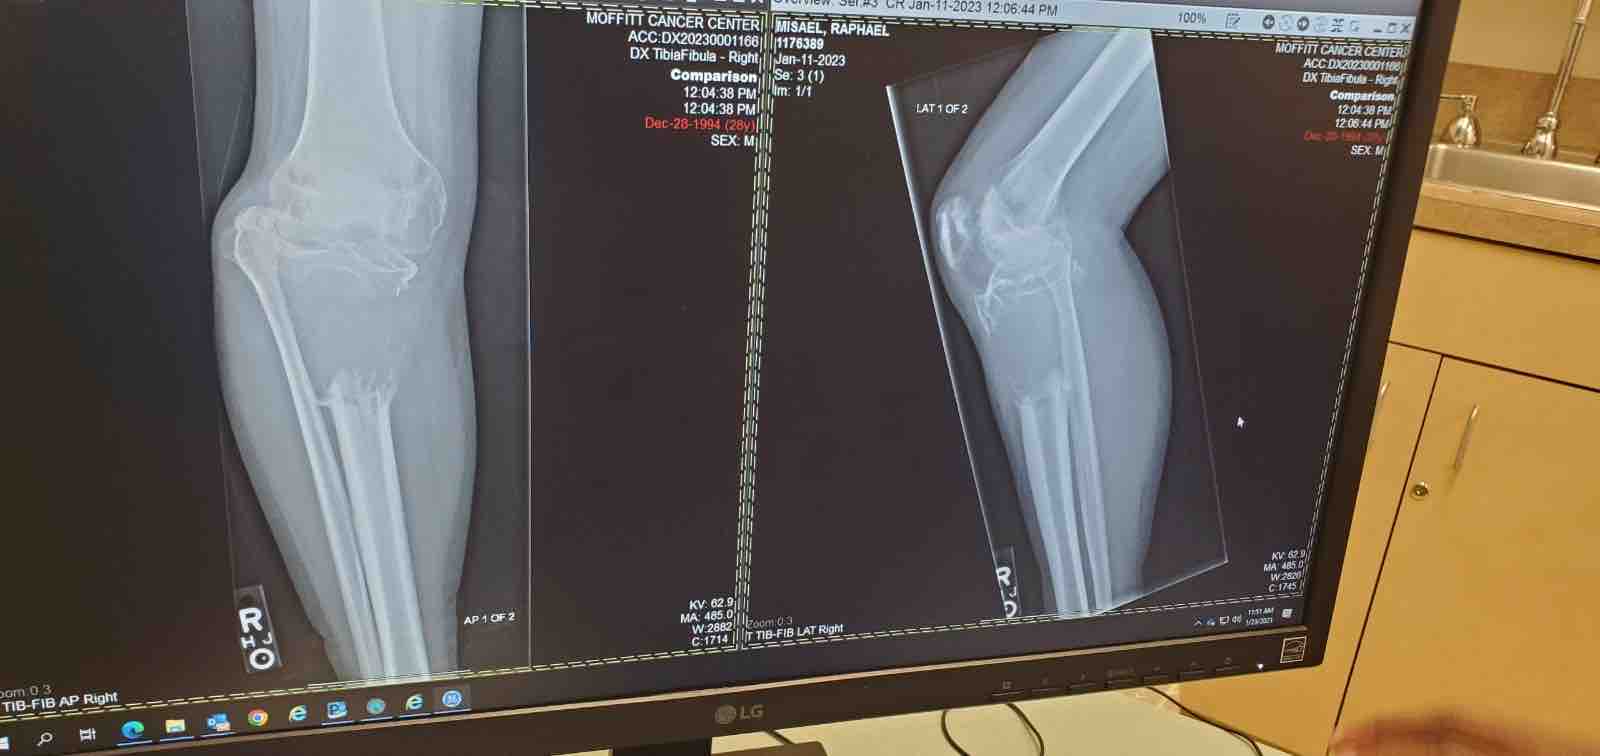

Hello everyone, I am raising funds to help pay for cancer treatment and a prosthetic. Last October I was diagnosed with bone cancer in my right leg after a tumor grew and destroyed a huge portion of bone in my tibia. The cancer had spread to my lungs resulting in a classification of “Stage 4” upon diagnosis. I started chemotherapy that same month and moved back from LA to Florida to be with family in December after a couple sessions. My mom has also been fighting cancer and spent all of last year fighting thru chemo and surgery.

Thankfully After 4 sessions of chemo my tumor shrunk and the cancer in my lungs went away but my tibia bone is past fixing and our only choice is to remove the entire affected portion from my leg. I will need to use a prosthetic for the rest of my life.

I have been on crutches since April 2022 because the tumor started growing around that time and broke my leg which led to the discovery of said tumor. I was unable to begin any serious treatment for 6 months due to issues with medical insurance.